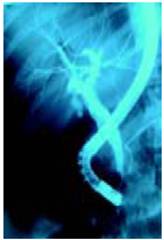

Vẫn còn nghi ngờ viêm đường mật do sỏi, nên các thầy thuốc đã chỉ định thuốc kháng sinh Ceftriaxone 2 g/ngày tiêm tĩnh mạch và sau đó chuyển bênh nhân đến khoa nội soi để xem xét thêm cho rõ ràng thông qua thực hiện thủ thuật nội soi mật tụy ngược dòng (ERCP_endoscopic retrograde cholangiopancreatography). Sau khi đặt canule chọn lọc vào cho thấy đường mật chủ bị lấp đầy bởi một vật cản quang (contrast agent) và có biểu hiện đó là các vật thể hình oval, di động hơi lớn đáng chú ý. Đường mật trong gan có kích thước bình thường.